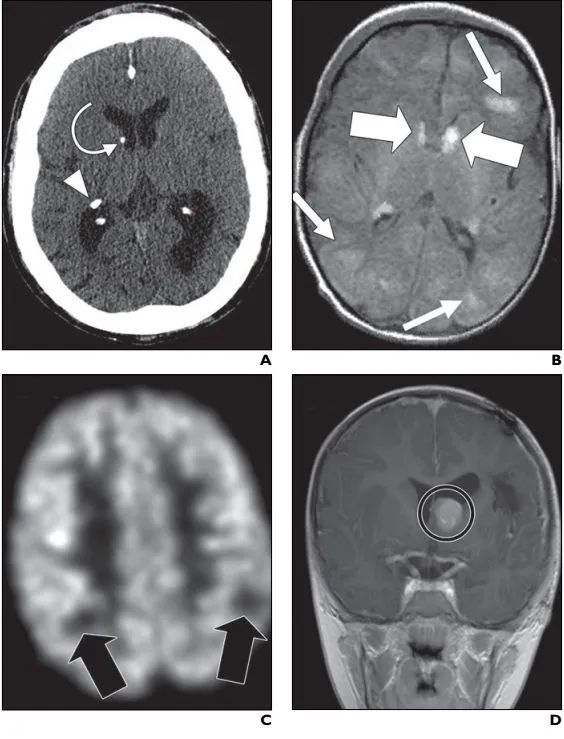

注:A:CT图像显示位于右侧丘脑尾侧沟(箭)和右侧丘脑后外侧(箭头)钙化的室管膜下结节。B:FLAIR MR图像显示多发高信号皮层和皮层下结节(细箭)和沿着侧脑室前角排列的高信号室管膜下结节(粗箭)。C:FDG PET图像显示葡萄糖区域低代谢区域(箭),对应着致痫结节。D:结节切除后冠状位对比剂增强MR图像显示位于左侧脑室Monro孔(圆圈)的明显强化的室管膜下巨细胞性星形细胞瘤和伴随的轻度脑积水。